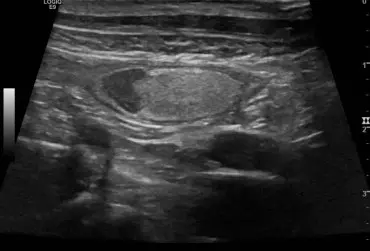

Rzekomołożyskowy przerost błony śluzowej macicy u suk w badaniu ultrasonograficznym

Rzekomołożyskowy przerost błony śluzowej macicy jest rzadko występującą formą przerostu endometrium występującą u młodych suk. Opisano przypadek występowania tej formy przerostu u 18-miesięcznej suki rasy flat coated retriever z wieloma nieswoistymi objawami, w tym przedłużającą się cieczką. W badaniu USG wykryto obecność pięciu zmian miejscowych w rogach macicy w postaci hipoechogennej, pogrubiałej błony śluzowej z obecnością ognisk i pasm hiperechogennych prostopadłych do osi długiej macicy oraz nietypową, hiperechogenną warstwę w centrum. Obraz zmian odpowiadał rzekomo łożyskowemu przerostowi endometrium, natomiast obecność hiperechogennej, wewnętrznej warstwy błony śluzowej macicy mogła wynikać z długości czasu trwania estrus. Zastosowano leczenie zachowawcze aglepriston podawanym podskórnie. Zmiany istotnie zmniejszyły się po zakończeniu leczenia, po czterech miesiącach nie były widoczne.